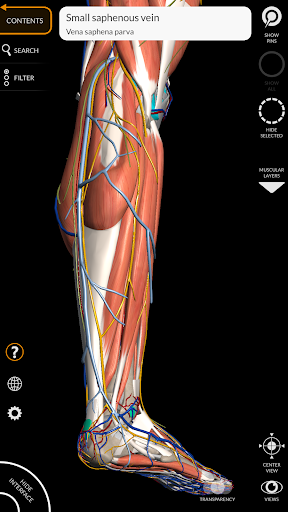

"Anatomy 3D Atlas" memungkinkan Anda mempelajari anatomi manusia dengan cara yang mudah dan interaktif.

Melalui antarmuka yang sederhana dan intuitif, Anda dapat mengamati setiap struktur anatomi dari sudut mana pun.

Model 3D anatomi sangat terperinci dan memiliki tekstur hingga resolusi 4k.

Pembagian berdasarkan wilayah dan tampilan yang telah ditetapkan sebelumnya memudahkan pengamatan dan studi bagian tunggal atau kelompok sistem dan hubungan antara organ yang berbeda.

MODEL ANATOMI 3D

saraf • Sistem pernapasan • Sistem pencernaan • Sistem urogenital (pria dan wanita) • Sistem endokrin • Sistem limfatik • Sistem mata dan telinga FITUR • Antarmuka yang sederhana dan intuitif • Putar dan perbesar setiap model dalam ruang 3D • Opsi untuk menyembunyikan atau mengisolasi satu atau beberapa model yang dipilih • Filter untuk menyembunyikan atau menampilkan setiap sistem • Fungsi pencarian untuk menemukan setiap bagian anatomi dengan mudah • Fungsi penanda untuk menyimpan tampilan khusus • Rotasi cerdas yang menggerakkan pusat rotasi secara otomatis • Fungsi transparansi • Visualisasi otot melalui tingkat lapisan dari yang superfisial hingga yang terdalam • Dengan memilih model atau pin, istilah anatomi terkait akan muncul • Deskripsi otot: asal, • Tampilkan/ Sembunyikan antarmuka UI (sangat berguna dengan layar kecil) MULTIBAHASA • Istilah anatomi dan antarmuka pengguna tersedia dalam 11 bahasa: Latin, Inggris, Prancis, Jerman, Italia, Portugis, Turki, Rusia, Spanyol, Mandarin, Jepang, dan Korea • Istilah anatomi dapat ditampilkan dalam dua bahasa secara bersamaan PERSYARATAN SISTEM • Android 8.0 atau yang lebih baru, perangkat dengan RAM minimal 3GB Reversi